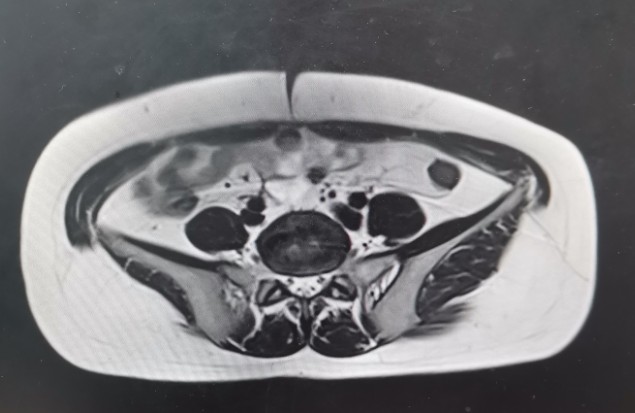

•全腹核磁:子宫术后改变,脂肪肝,双肾囊肿,盆腔少量积液。

轴位T1

轴位T2